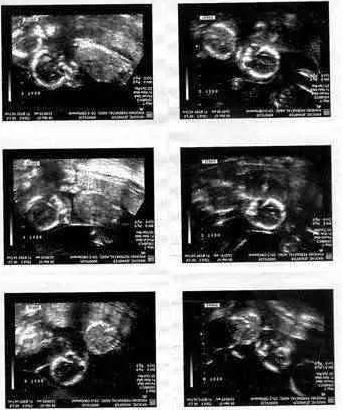

Doktor Janet ve Graham çiftine bir tane değil tam 6 tane bebeklerini olacağını söylemişti. Graham ve Janet çifti doktorun bu söylediği karşısında dilleri tutuldu. Yıllardır çocuk sahibi olmak isteyen çift şimdi 6 çocuk sahibi olacaktı. Anne-Baba olma hasreti ile 6 çocuk için mutlu olan çiftin tek korkusu bu doğumun tehlikeli olmasıydı ve 6 çocuk doğurmak gerçekten tehlikeliydi. Janet doğumundan çok önce hastaneye yatırılarak gözetim altında tutuldu. Haftalarca hastanede gözetim altında tutulan Janet en sonunda 18 Kasım 1983 yılında 6 çocuk dünyaya getirdi. Liverpool’da bir hastanede dünyaya gelen bebekler sezaryen operasyonu ile anne karnından alınmışlardı.

Dünyada ilk kez altız olarak doğan ve tüm dünyanın dikkatini çeken bu doğum sonrası bebekler ile anne hastanede tedavi altında kalmaya devam ettiler. Birkaç aylık tedavi sonrası anne ile 6 bebeği hastaneden taburcu edildiler. Tüm dünya bu haberi gazetelerden periyodik olarak takip ediyorlardı ve artık Ruth, Hnnah, Kate, Lucy, Sarah ile Jennie tüm dünyaca bilinen 6 kız kardeş olmuşlardı.